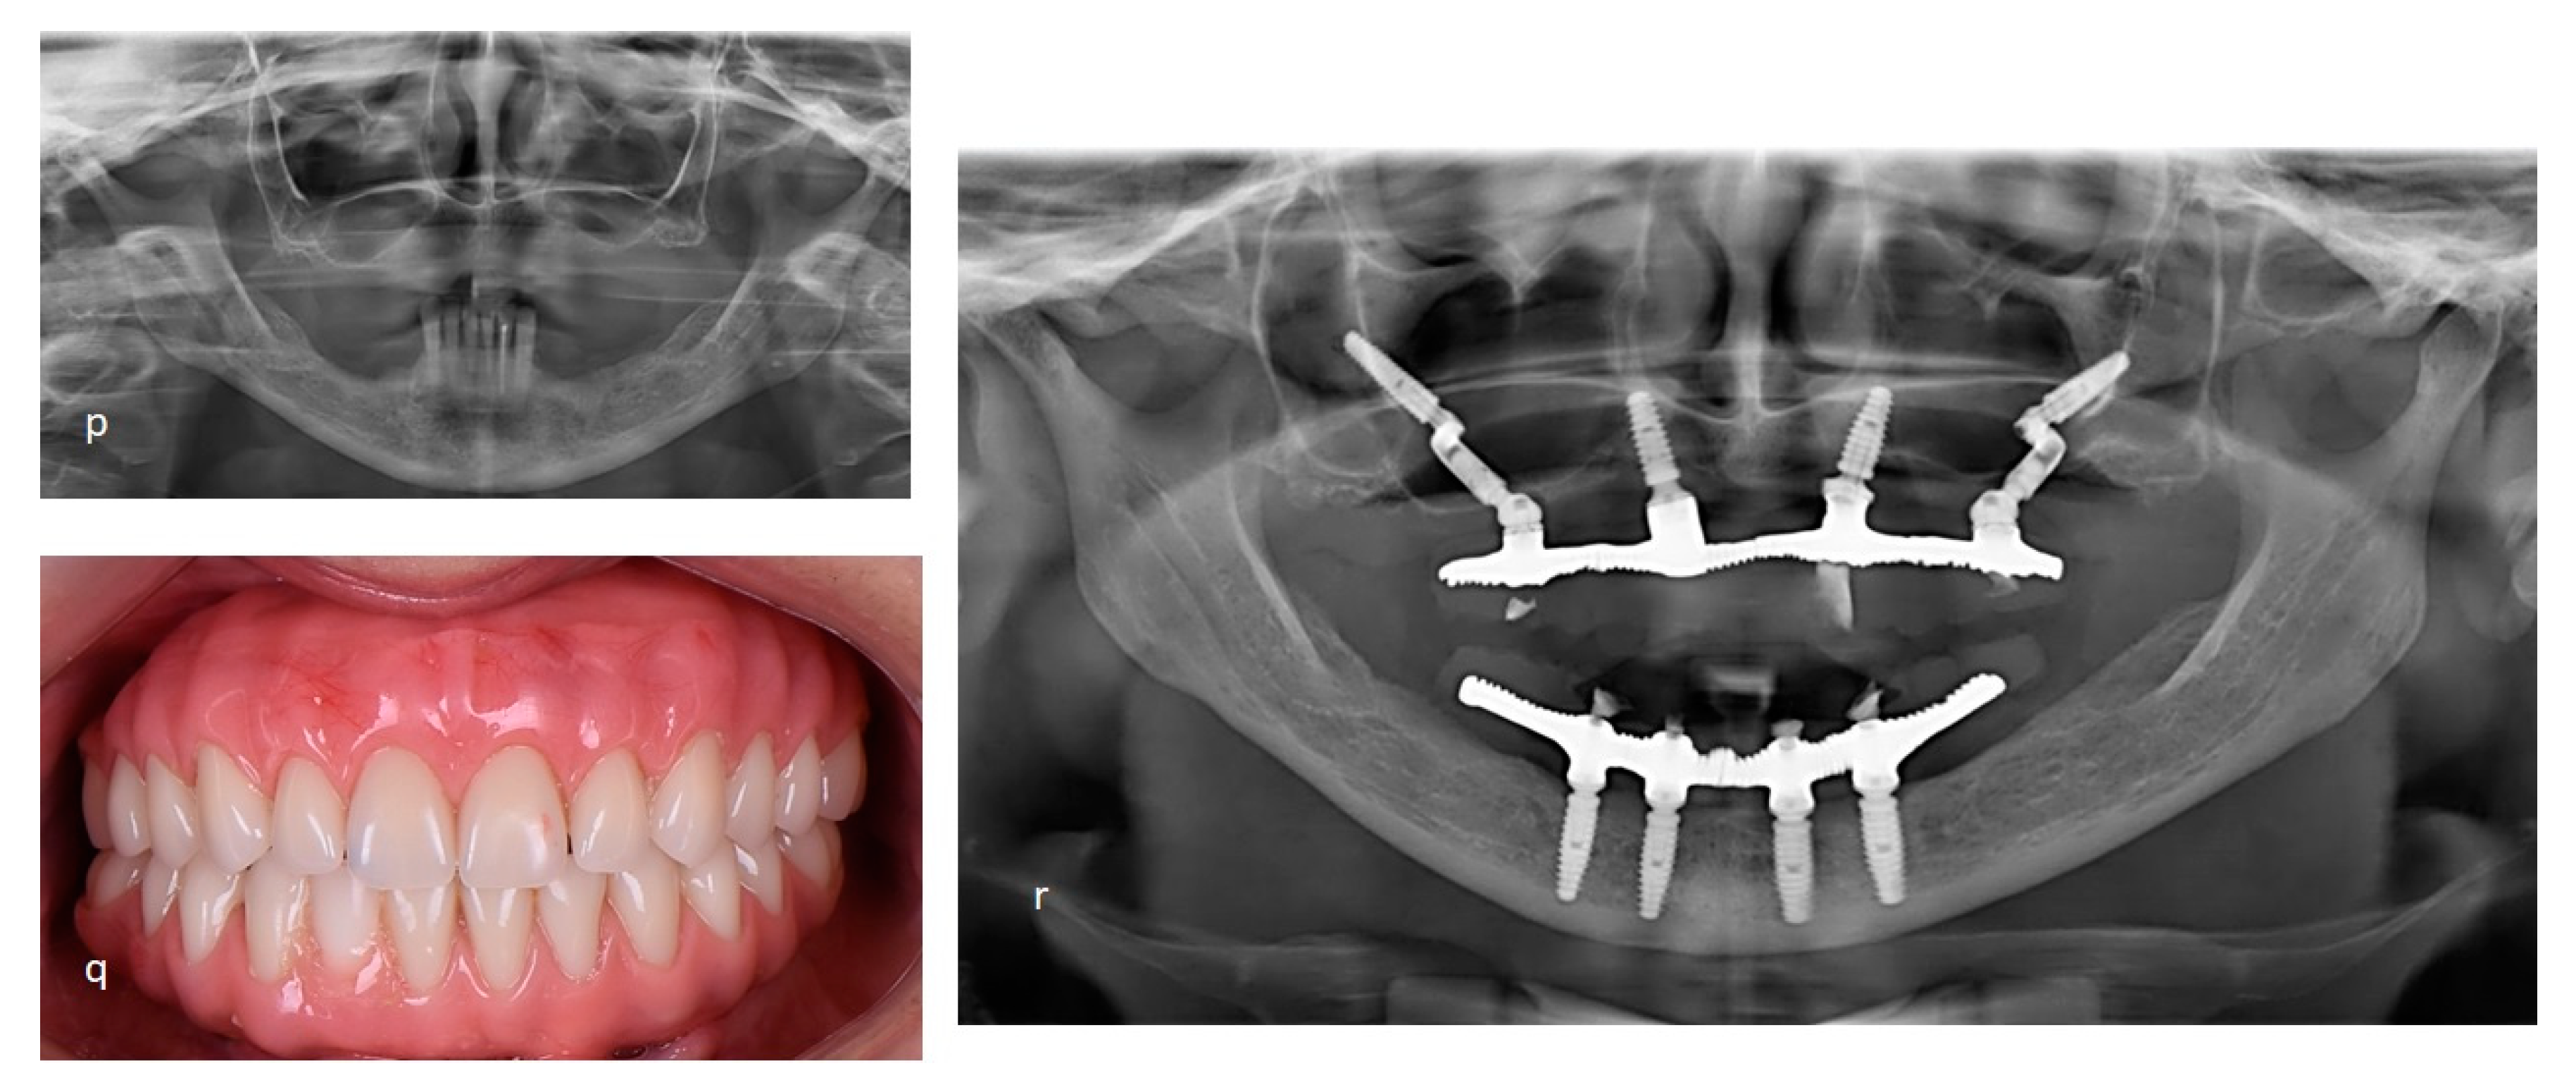

Figure 7.

The second case report shows the Facco technique used to rehabilitate a female patient, 58 years, without teeth or implants at atrophic maxilla and monitoring by 36 months after the surgical. A. Infiltrative anestesia at zygomatic arch. B. Incisions nealy zygomatic arch. C. Displacement gingival flap and suture to facilitate access at zygomatic area. D-G. Surgical sequence at right side until the setup pilar Z. H. Initial evaluation of the zygomatic boné. I. Milling cavity at zygomatic arch. J-M. Surgical sequence at left side. N. Implants positions favoring the posterior prosthetic rehabilitation. P. Initial panoramic radiography showing atrophic maxilary. Q. Final photo. R. Panoramic radiography final showing all-on-4 by Facco techinique.